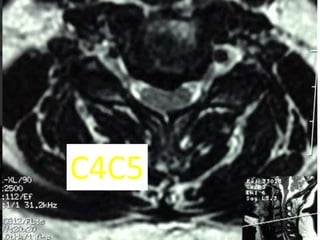

c4c5